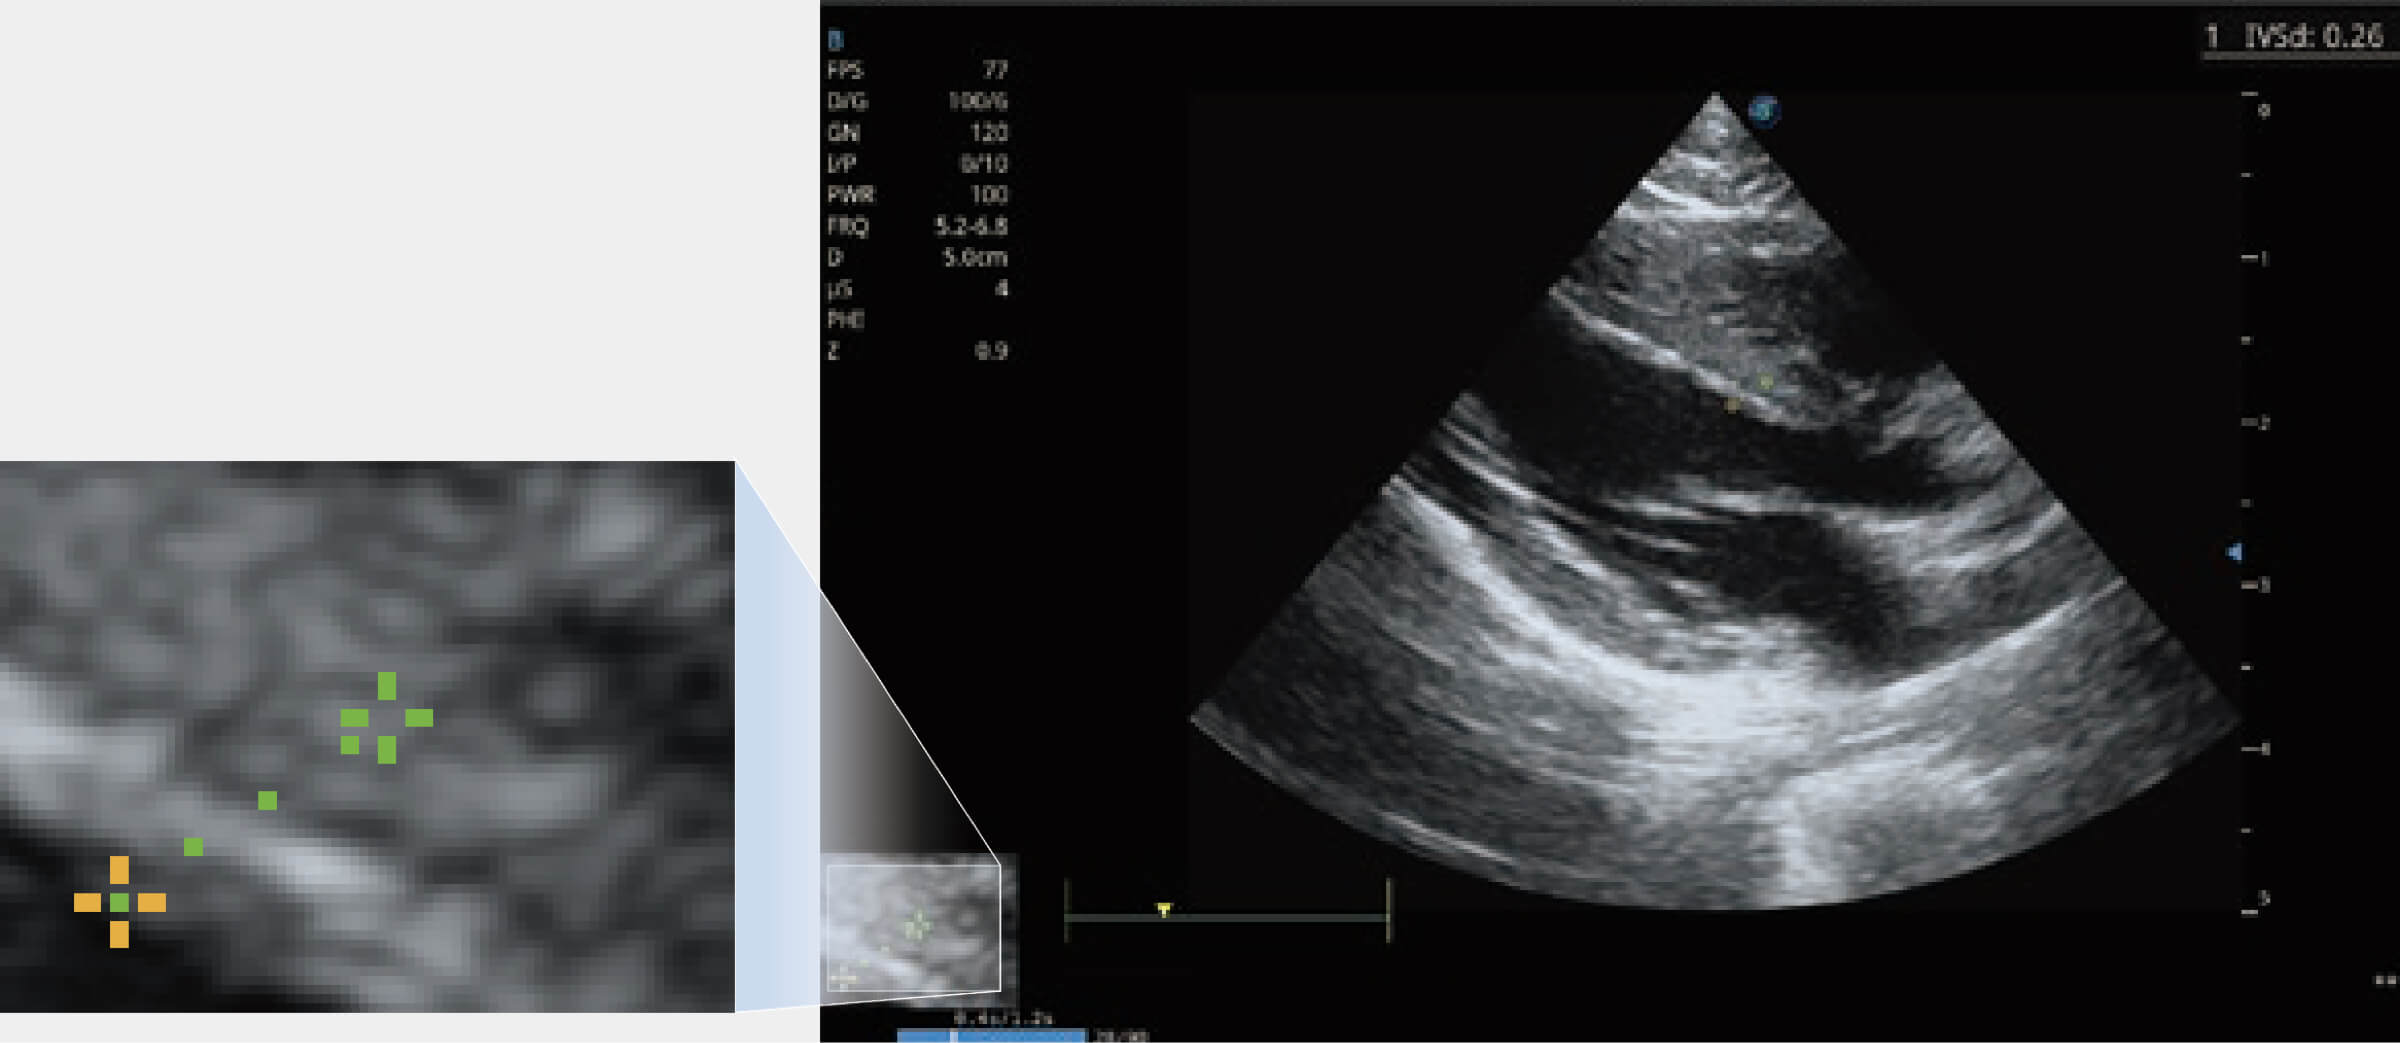

通過(guò)心肌識(shí)別技術(shù)與二維斑點(diǎn)追蹤技術(shù)相結(jié)合,對(duì)心臟的超聲圖像進(jìn)行量化分析。計(jì)算心肌17個(gè)節(jié)段的應(yīng)變、應(yīng)變率、速度、位移等,并通過(guò)牛眼圖的形式進(jìn)行呈現(xiàn)。

能夠基于左心室壁追蹤和辛普森法,自動(dòng)計(jì)算射血分?jǐn)?shù),支持多個(gè)可移動(dòng)點(diǎn)描跡,與手動(dòng)測(cè)量相比,極大節(jié)省了動(dòng)物醫(yī)生的時(shí)間和精力。